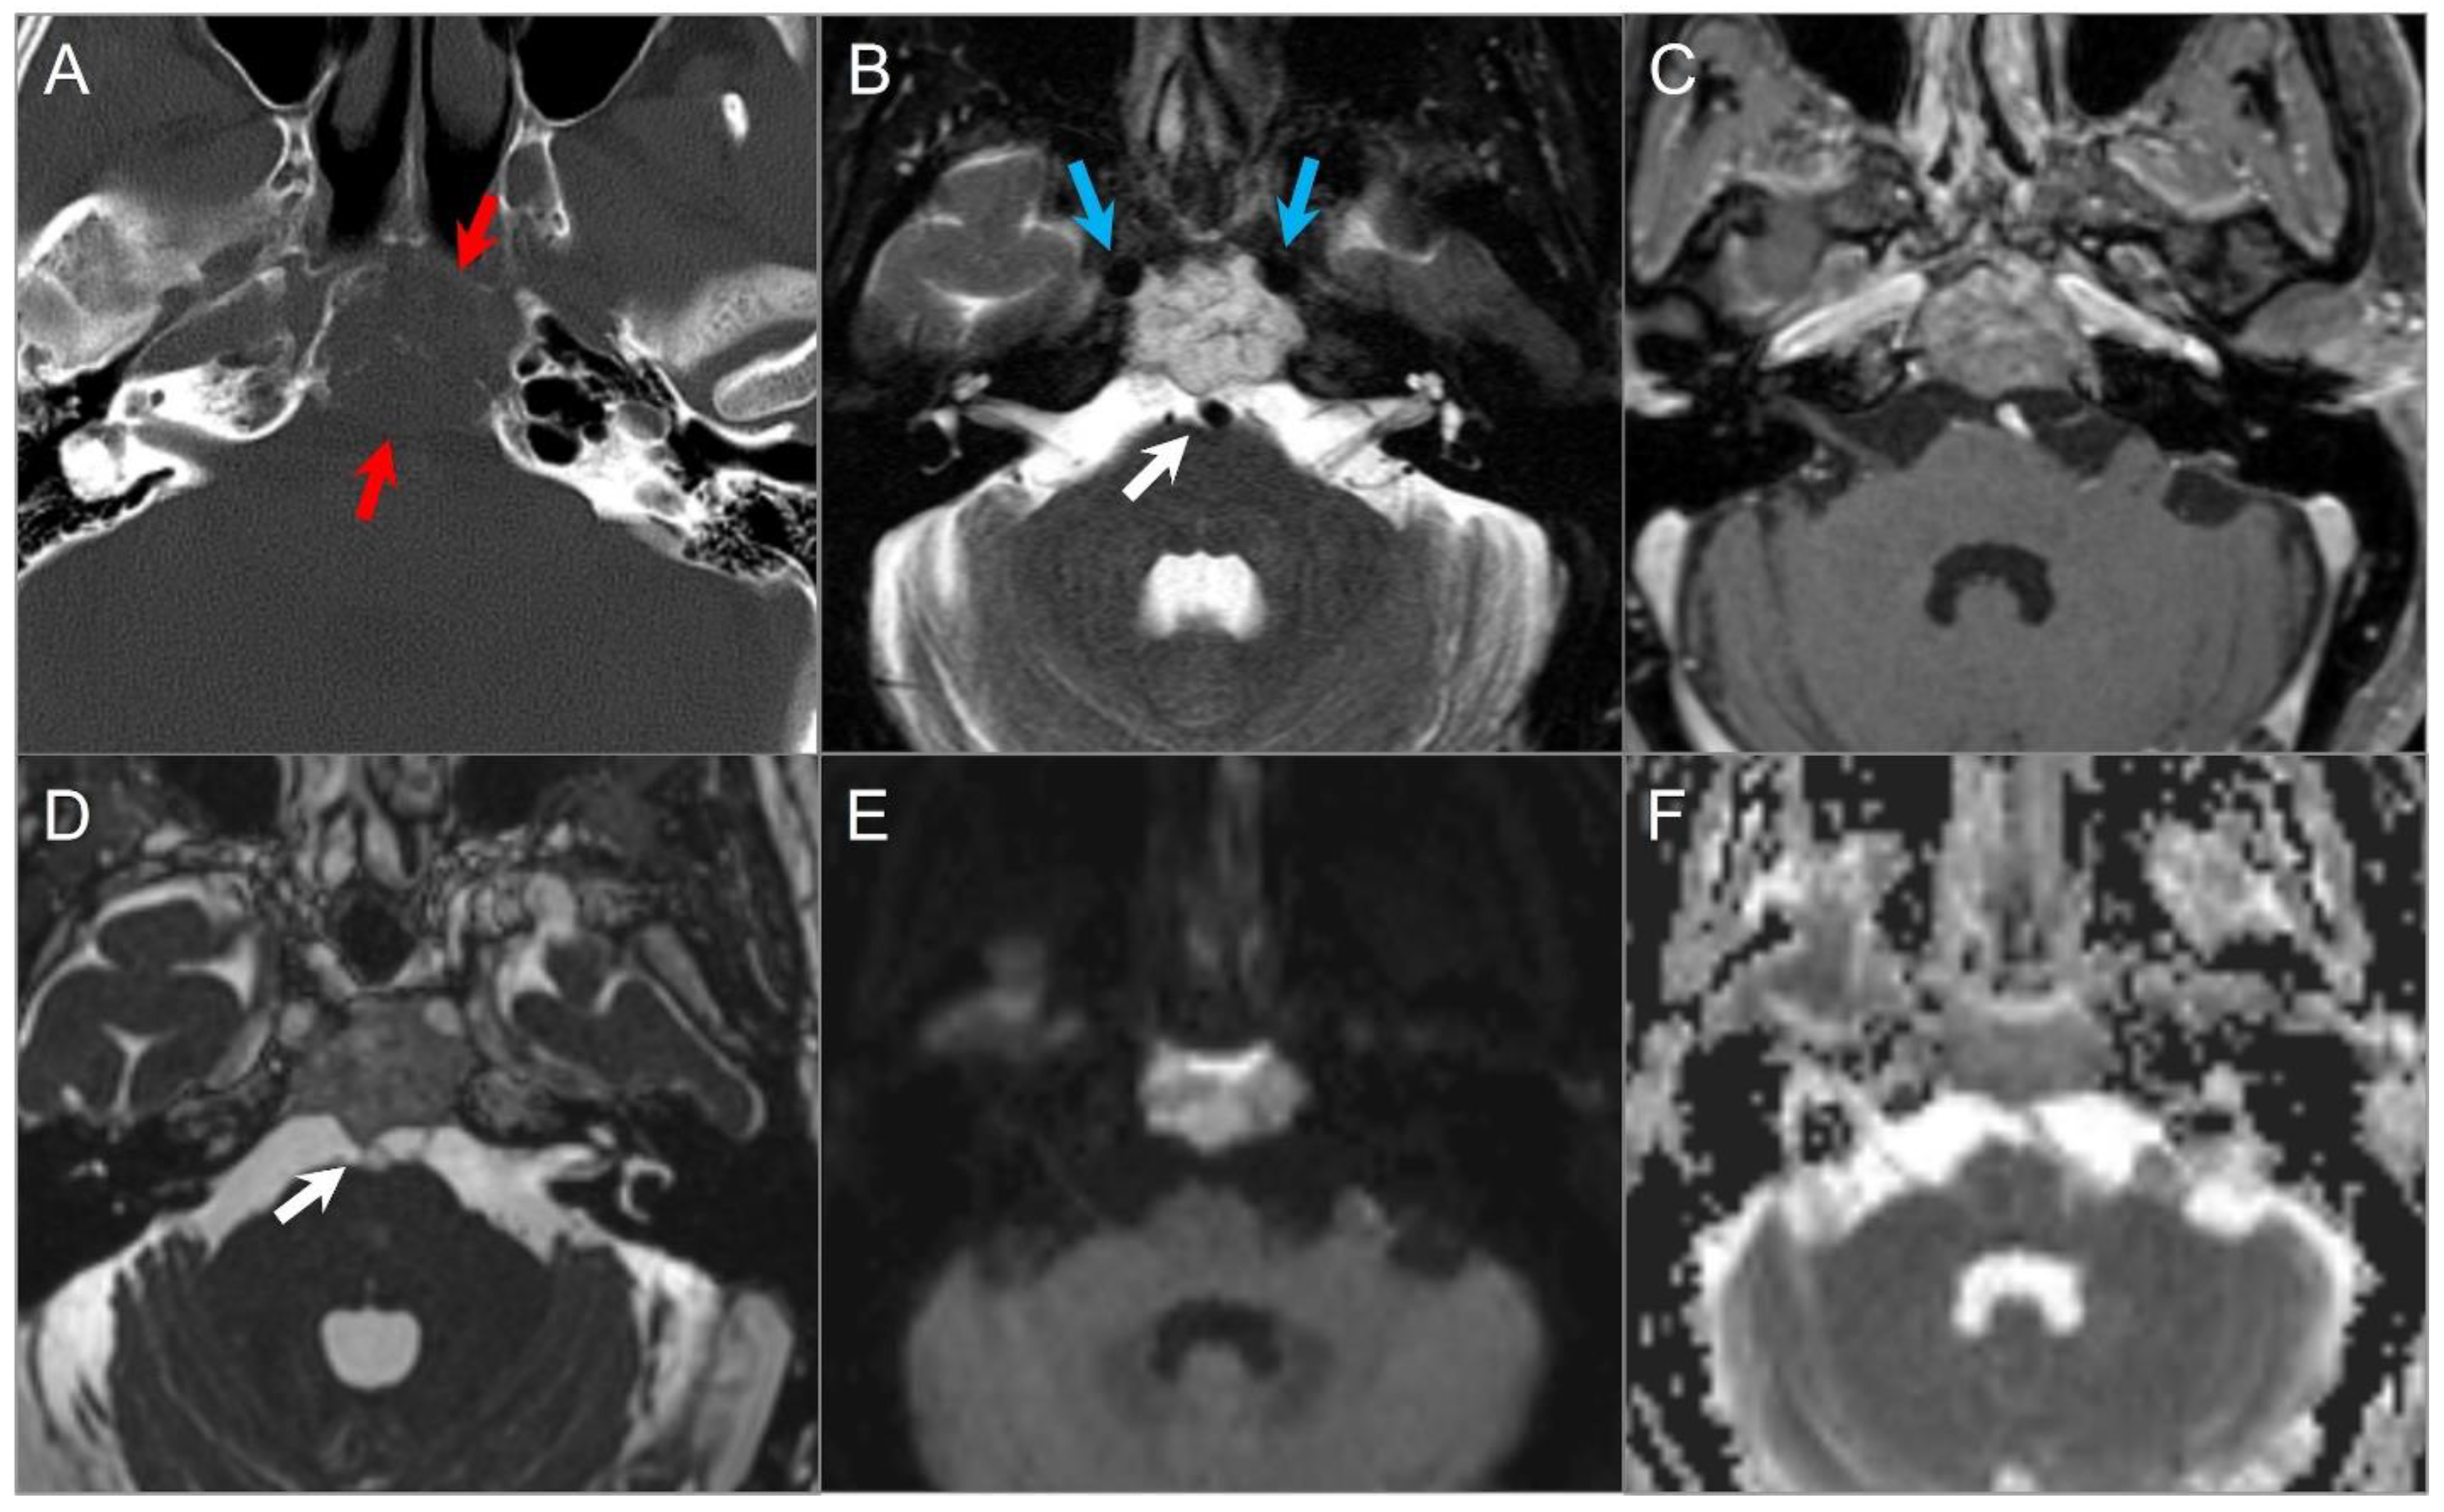

4.4.1. Chordoma

4.4.2. Chondrosarcoma